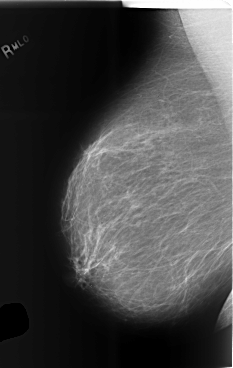

C_0496_1.RIGHT_MLO

RIGHT_MLO LINES 5880 PIXELS_PER_LINE 3720 BITS_PER_PIXEL 12 RESOLUTION 50 NON_OVERLAY